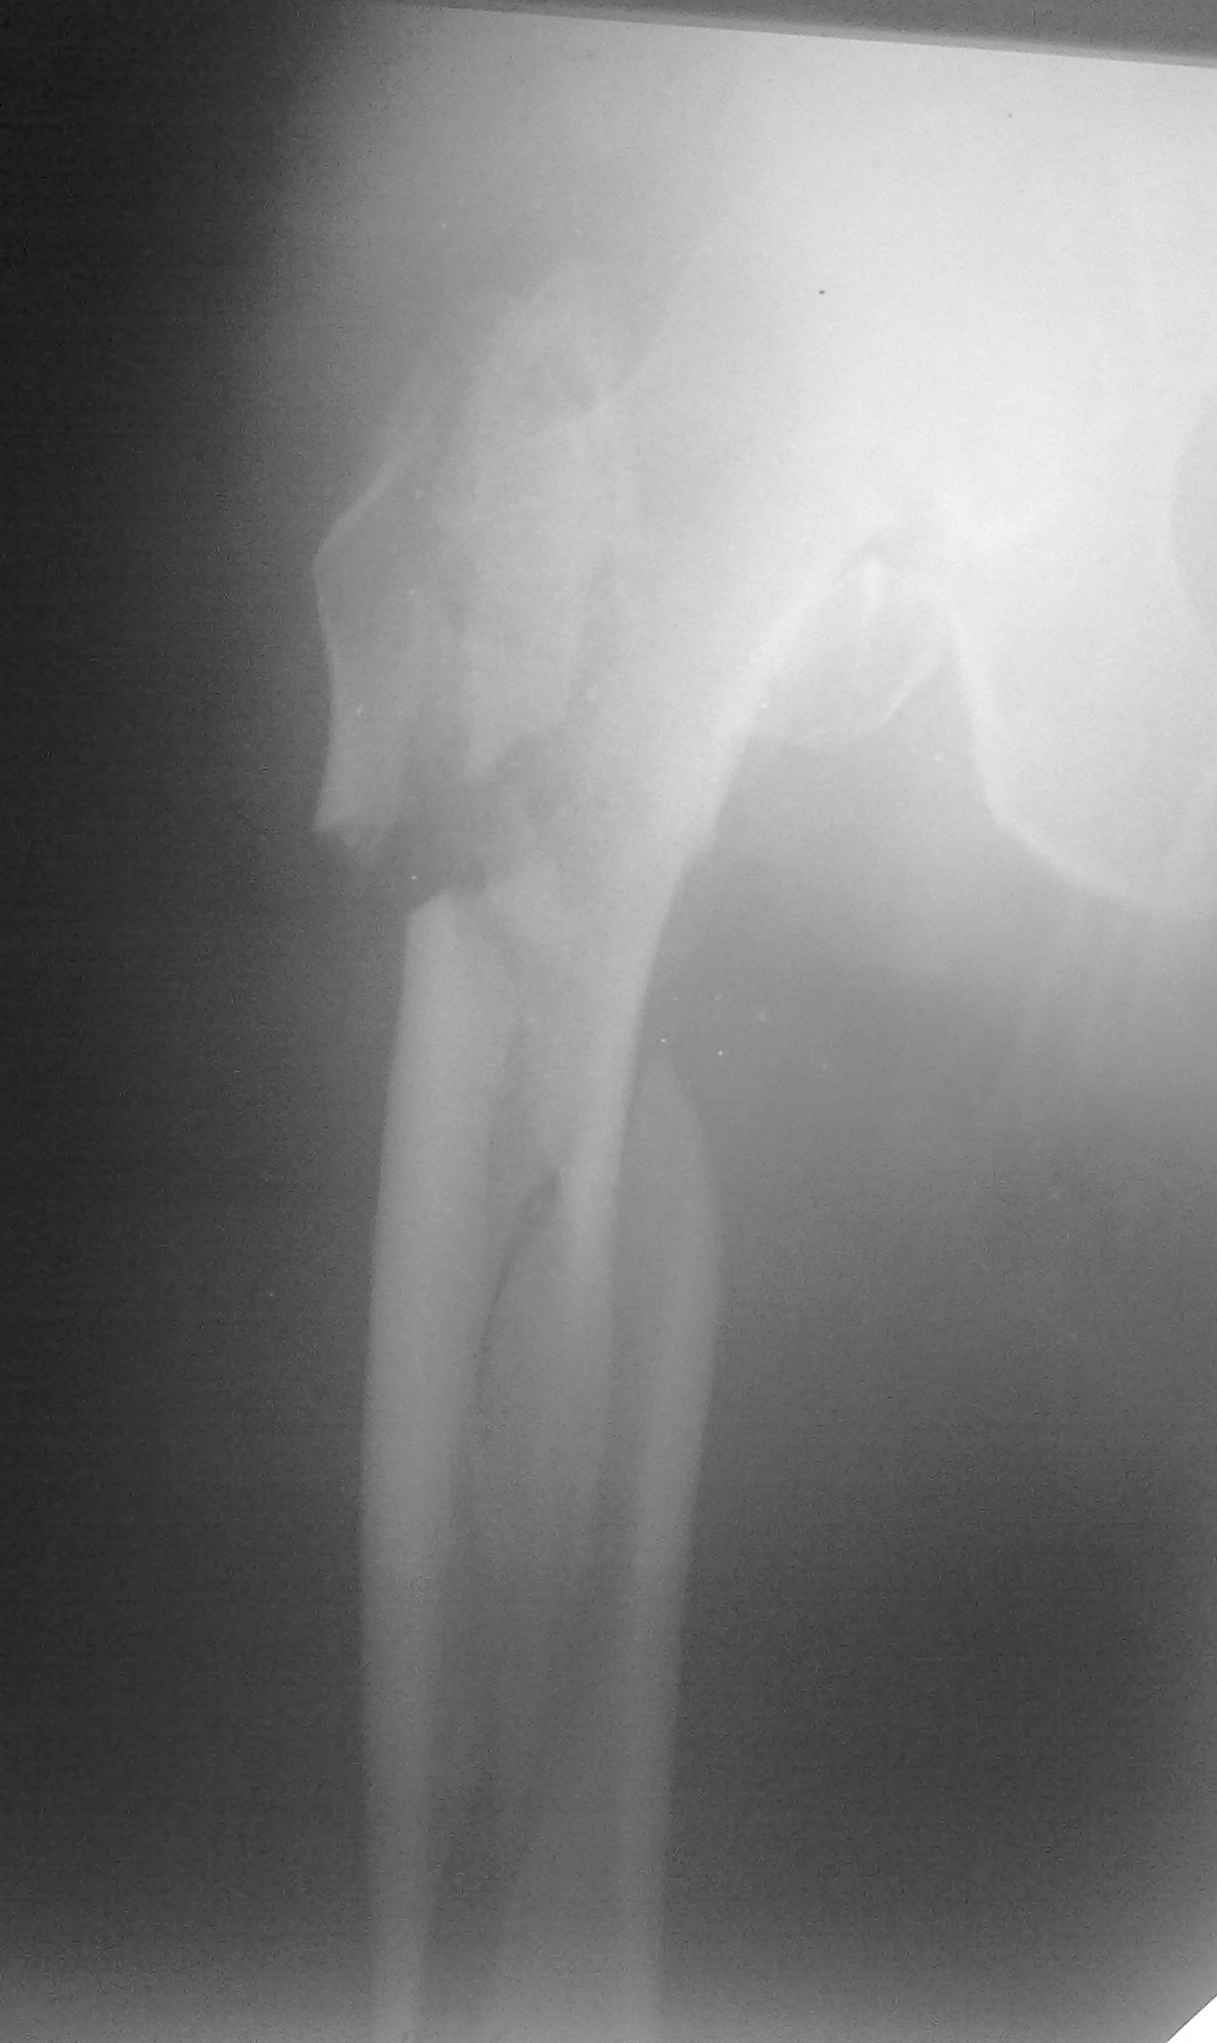

Пациент 83 года. Реконструктивный бедренный стержень Chm

коллеги в наличии есть только проксималный гвоздь chm длинна 260мм.отправить мы ее тоже никуда не можем т.к в облати внедряется тока у нас

Короткая версия 240 мм. Длинные начинаются с 260 мм? Попробуйте имеющуюся железку приложить к рентгенограмме - скорее всего, 260 мм будет маловато. Должна быть возможность связаться с поставщиком и поменять имеющийся гвоздь на аналогичный нужного размера.

День добрый! 240 мм однозначно короток, нужен миниум 300 мм, а то благие начинания заведут вас в ад осложнений. С диабетом на операции открывть ничего не нужно, только закрытая репозиция на ортопедическом столе под контролем ЭОПа. Без 100% анатомичной репозиции. Восстановить ось и ШДУ.